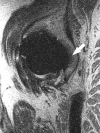

Background: Little is known about intraarticular pathology following THA prior to the radiographic appearance of osteolysis, primarily due to imaging limitations. MRI has recently been applied to imaging the postarthroplasty hip with the ability to detect periarticular bony and soft tissue pathology; specifically, it is able to detect abnormal synovial patterns and focal bone loss well before the radiographic appearance of osteolysis.

Methods: We recruited 31 patients (33 hips) who underwent routine noncemented THA with one of three types of bearing surfaces: metal-on-cross-linked polyethylene (n = 7), ceramic-on-ceramic (n = 12), and ceramic-on-cross-linked polyethylene (n = 14). Patients underwent specialized MRI at a minimum of 12 months (mean, 23 months; range, 12-37 months) after surgery. MR images were analyzed for the presence of synovitis or osteolysis. WOMAC scores, patient assessment questionnaires, and radiographic wear measurements were correlated with MRI findings.

Results: Reactive synovitis was observed in 13 of 33 patients (39%) and focal osteolysis in one of 33 (3%). The presence of synovitis did not correlate with pain, activity level, patient satisfaction or clinical outcome scales, nor did it correlate with radiographic wear measurements at early followup.